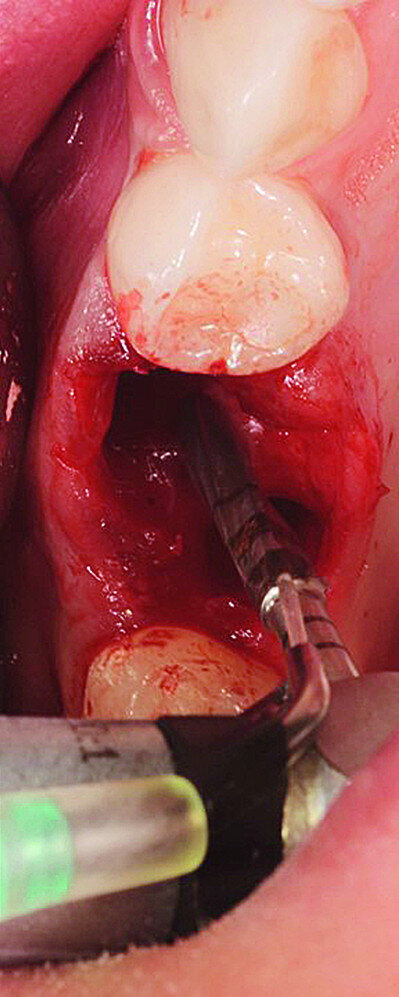

The surgical treatment phase started with extraction of tooth #16, followed by excision of the root cyst and alveolar curettage (Figs. 4a & b). For good disinfection of the alveolus, ozone therapy (Ozone DTA, Apoza) was applied (Fig. 4c), taking into account the antimicrobial action of ozone, which prevents the development of the inflammatory process, favouring cellular recovery and consequently improving the postoperative healing. Once the alveolus had been disinfected, the implant bed was prepared with a sequence of implant drills from the AnyRidge surgical system (AnyRidge Surgical Kit, MegaGen; Fig. 4d). The bone defects were filled with a bone xenograft of porcine origin (Gen-Os, OsteoBiol), mixed with i-PRF (injectable platelet-rich fibrin; PRF process by Choukroun; Figs. 5a & b). Afterwards, bone densification was performed through a sequence of Densah drills (Densah Burs, Versah; Fig. 6a). This type of drill allows the clinician to perform a bone densification process.